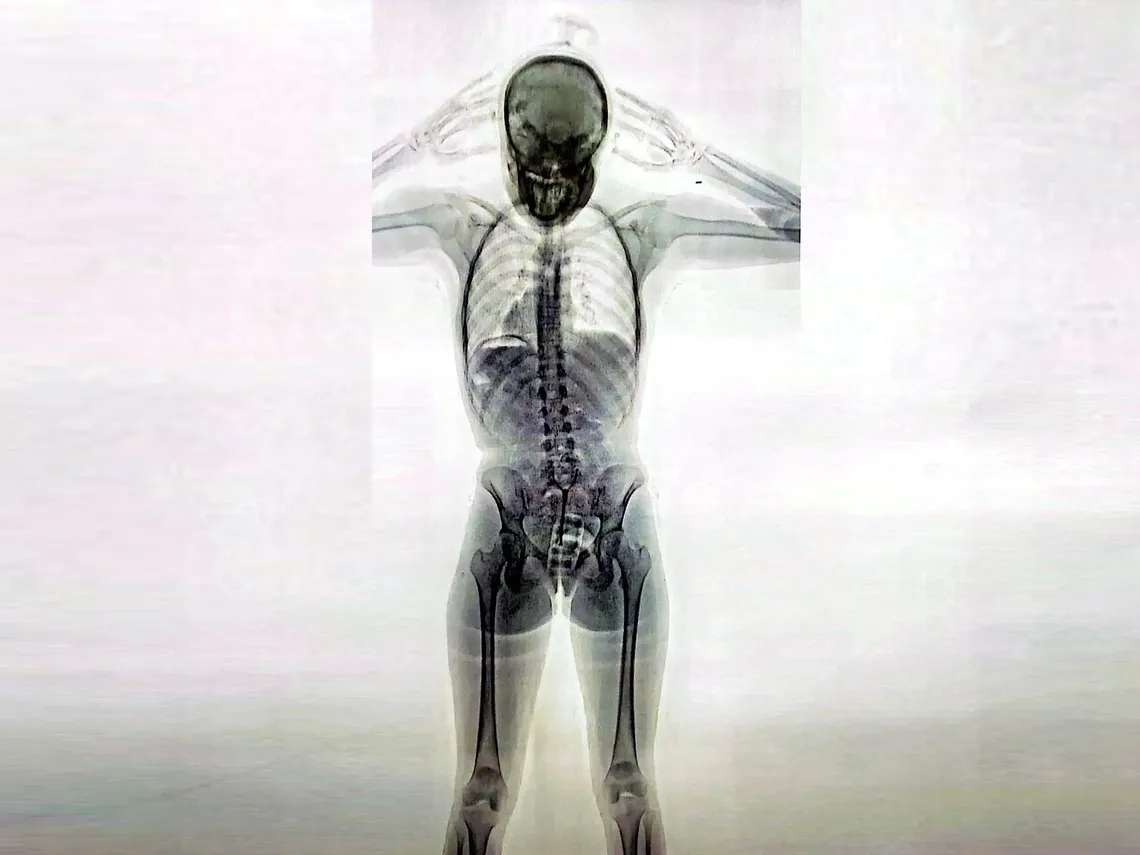

“Hace unas horas fue detenida ‘Ornella’, una chica de 20 años del barrio porteño de Villa del Parque, en el Aeropuerto Internacional de Ezeiza para tomar el vuelo IB 2602 de la empresa Level rumbo a Barcelona, España. La Policía de Seguridad Aeroportuaria (PSA) sospechó de su nervioso comportamiento, la sometió a rayos X y encontró que llevaba 11 cápsulas (unos 110 gramos de cocaína) dentro de un profiláctico que había colocado dentro de su vagina«, reveló Javier Miglino, director de DBA.

«Más 67 cápsulas más que estaban distribuidas por todo su aparato digestivo. Una verdadera bomba de tiempo, porque si sólo una de las cápsulas se abría durante el vuelo, algo que suele ocurrir por el pico de estrés, el cambio de presión atmosférica y la imposibilidad de encontrar una postura natural, la muerte llega en pocos minutos. Sin embargo, el caso de «Ornella» es solo uno de los casi 70 que han intentado llevar drogas a Europa y en particular al verano europeo”, relató el abogado.